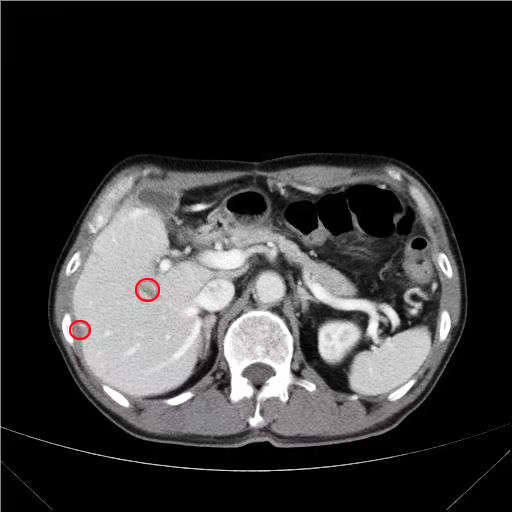

影像2022